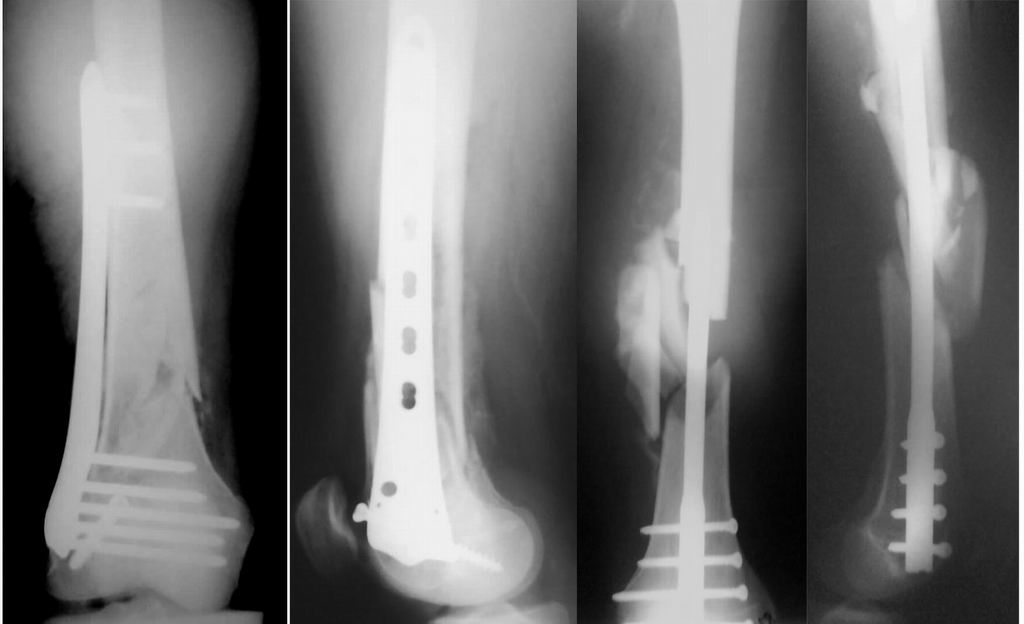

Уважаемые коллеги! От имени Алексея Смирнова всем спасибо за обсуждение. Больной прооперирован. Снимки в приложении.